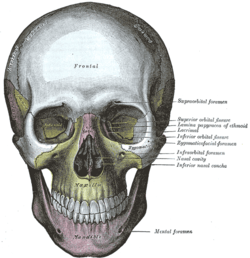

Side view of the skull. The skull from the front.

The skull from the front. Horizontal section of nasal and orbital cavities.